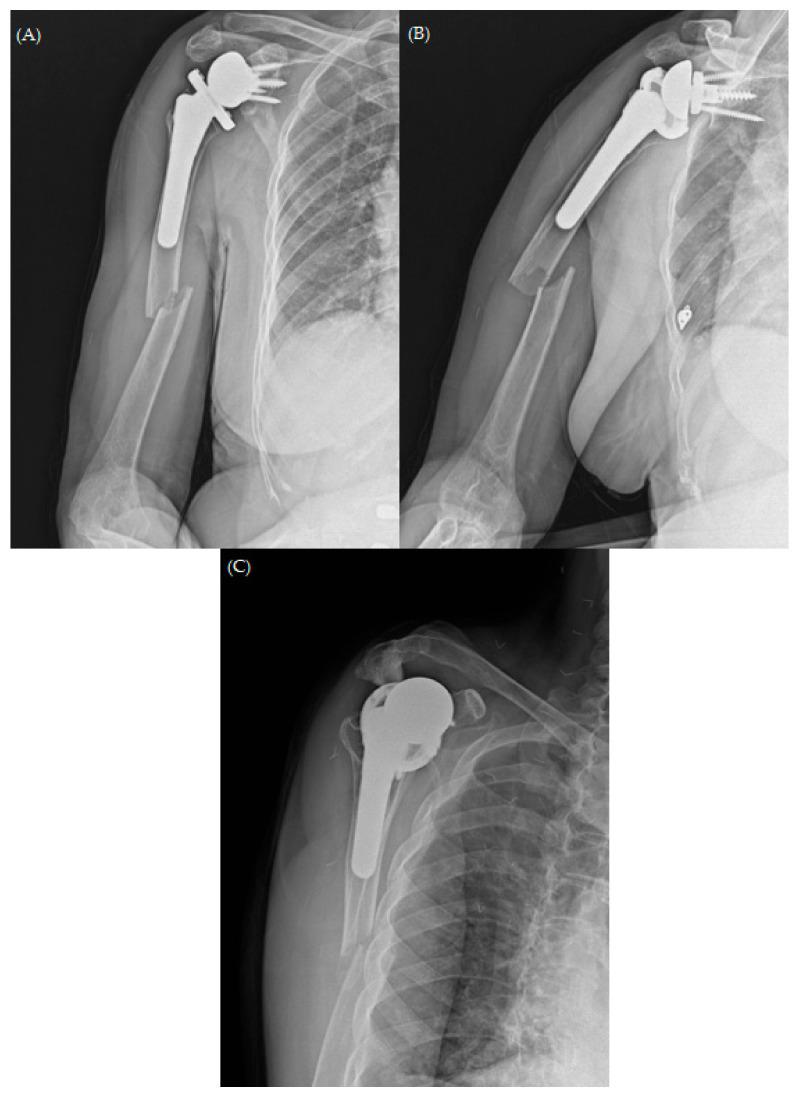

Periprosthetic fractures are a serious complication of joint replacement surgery. With the growing prevalence of reverse total shoulder arthroplasty (RTSA), the incidence of relatively uncommon periprosthetic humeral fractures has increased. Here, we present the unique case of a 74-year-old woman who developed atrophic non-union after plate osteosynthesis for a periprosthetic fracture associated with RTSA. Fixation failure was evident 3 months after the surgical intervention; the patient underwent a 3-month course of arm sling immobilization. However, bone resorption continued, and varus angulation of the fracture developed. In this case, surgical strategy involved the use of long proximal humerus internal locked system plate (DePuy Synthes, Paoli, PA, USA), augmented with autologous iliac bone graft and allogenic humerus structural bone graft with the "bamboo support technique", fixed with Cable System (DePuy Synthes, Paoli, PA, USA). No reports have addressed the management of failed periprosthetic fractures using allogeneic humeral strut bone grafts. This report aims to fill the gap by presenting a novel surgical technique for the management of periprosthetic fractures associated with RTSA in case of treatment failure.

假体周围骨折是关节置换手术的一种严重并发症。随着反式全肩关节置换术(RTSA)的日益普及,相对罕见的假体周围肱骨骨折的发生率有所增加。在此,我们报告一例独特病例,一名74岁女性在因与RTSA相关的假体周围骨折行钢板内固定术后发生萎缩性骨不连。手术干预3个月后固定失败;患者接受了为期3个月的手臂吊带固定治疗。然而,骨吸收仍在继续,骨折出现内翻成角。在该病例中,手术策略包括使用肱骨近端加长锁定系统钢板(美国宾夕法尼亚州波利市DePuy Synthes公司),采用“竹节支撑技术”辅以自体髂骨移植和同种异体肱骨结构性骨移植,并使用线缆系统(美国宾夕法尼亚州波利市DePuy Synthes公司)进行固定。尚无关于使用同种异体肱骨支撑骨移植治疗失败的假体周围骨折的报道。本报告旨在通过介绍一种治疗失败情况下处理与RTSA相关的假体周围骨折的新颖手术技术来填补这一空白。